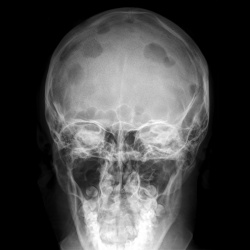

Интересный череп! Какие мнения будут?

08.06.2011 - 19:02

Уважаемые коллеги помогите разобраться!! Что это может быть??? Беспокоит с января месяца легкая асимметрия лица. Травму отрицает. Периодически беспокоят головные боли.

08.06.2011 - 12:01

ЛОРики пристати с диагнозом "образованием лобной пазухи (susp. neo)".